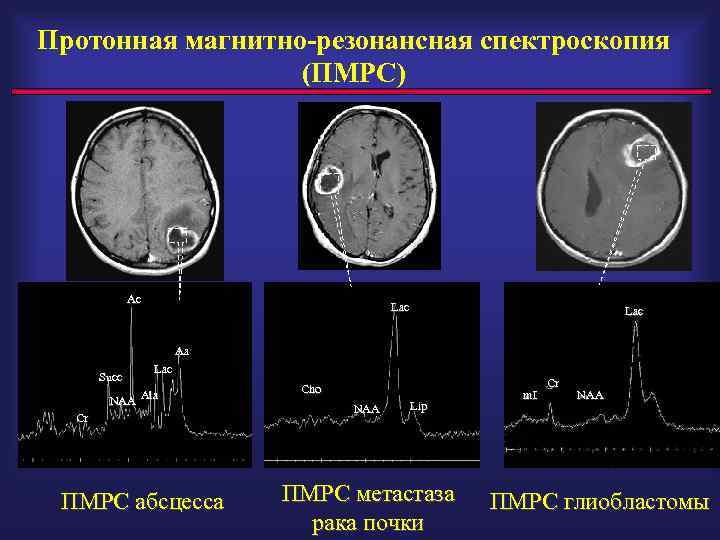

Протонная магнитно-резонансная спектроскопия (ПМРС) Ac Lac Aa Succ Lac Ala NAA Cr ПМРС абсцесса Cho NAA Lip ПМРС метастаза рака почки m. I Cr NAA ПМРС глиобластомы